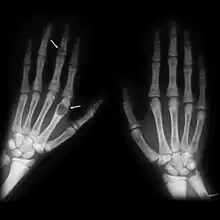

X-rays may also be used to diagnose the disease. Usually, these X-rays will show extremely thin bones, which are often bowed or fractured. However, such symptoms are also associated with other bone diseases, such as osteopenia or osteoporosis.[29] Generally, the first bones to show symptoms via X-ray are the fingers.[22] Furthermore, brown tumors, especially when manifested on facial bones, can be misdiagnosed as cancerous.[29] Radiographs distinctly show bone resorption and X-rays of the skull may depict an image often described as "ground glass" or "salt and pepper".[30][31] Dental X-rays may also be abnormal.[2]

Cysts may be lined by osteoclasts and sometimes blood pigments, which lend to the notion of "brown tumors." Such cysts can be identified with nuclear imaging combined with specific tracers, such as sestamibi.[3] Identification of muscular degeneration or lack of reflex can occur through clinical testing of deep tendon reflexes, or via photomotogram (an achilles tendon reflex test).[24][32]